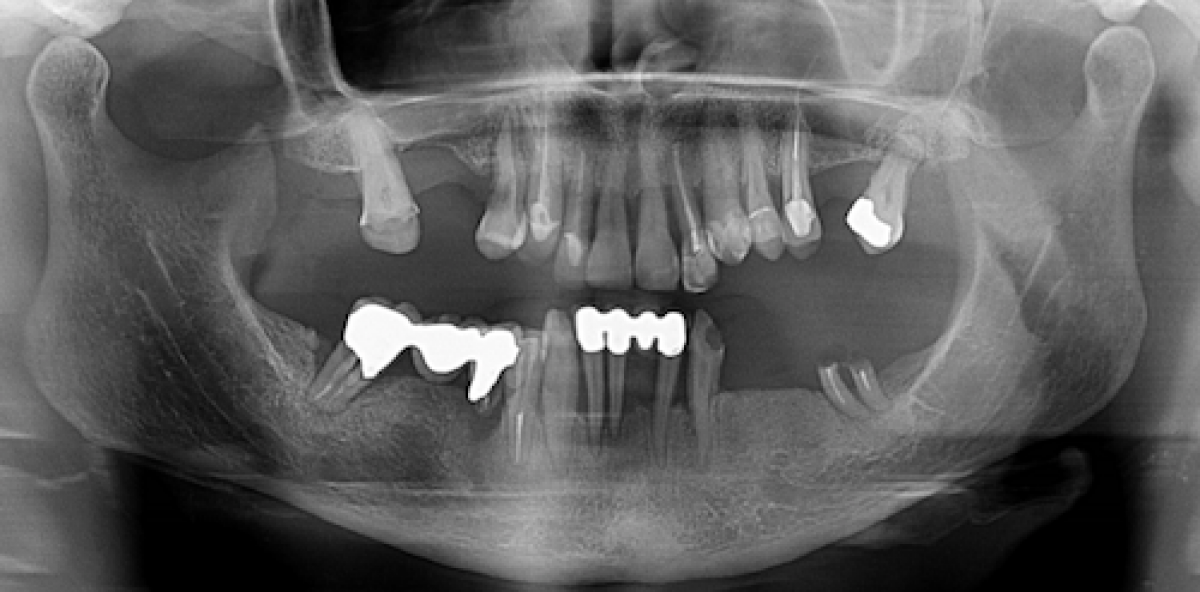

Periodontitis is a common chronic condition characterized by inflammation and loss of the supporting tissues around the teeth and it is a major cause of tooth loss. Development of periodontitis has been associated also with increasing age, being male, low economic status, frequency of visits to the dentist, smoking and alcohol consumption. Nonetheless dental plaque is the major cause of gingivitis and periodontitis. The composition of the plaque microflora changes over time due to a series of complex interactions and microbial succession.

Mechanical removal of the inter‐proximal plaque, by using floss, may be sufficient to stop the microbial succession process, that is associated with inflammation and disease initiation. A cross‐sectional study published on Journal of Clinical Periodontology in 2017 tried to examine the association between flossing and periodontitis.

A total of 6939 adult subjects were included. Of these subjects, 35% flossed no more than once in the past week. Men, younger subjects, current smokers, subjects with the lowest incomes and subjects who rarely visited a dentist flossed less frequently. 40% of the subjects had periodontitis. A higher percentage of subjects who flossed no more than once a week had periodontitis compared with subjects who flossed more often.

After adjustment, the odds of periodontitis were 17% lower for subjects who flossed >1 time a week than for subjects who flossed less often (odds ratio=0.83, 95% CI 0.72–0.97).

After adjustment for established risk factors and flossing, it was found that men are twice as likely as women to have periodontitis. Compared with subjects age 30–49, older subjects had higher odds of having periodontitis. For example, subjects 65 or older had three times the odds. Non‐smokers and former smokers had lower odds of having periodontitis than current smokers. The odds are 69% lower for non‐smokers than current smokers. Nonetheless former drinkers had higher odds of having periodontitis, compared with current drinkers. The odds of having periodontitis were 70% lower in subjects with the highest incomes than the lowest income. Visiting a dentist within the last year was associated with lower odds of having periodontitis, compared with subjects who never or rarely visit a dentist. The analyses in which the reference category was no flossing at all (instead of flossing no more than once a week) provided similar results. Compared with no flossing at all, flossing 1 or more days a week reduced the odds of having periodontitis by 23%.

This population‐based, observational study found that flossing was associated with a lower prevalence of periodontitis; a series of variables such as older age, being male, smoking, low income and less frequent dental visits are associated with a higher prevalence of periodontitis. Nonetheless, the benefit of flossing has been verified. This is a cross‐sectional study so a causal relation between flossing and periodontitis cannot be established.